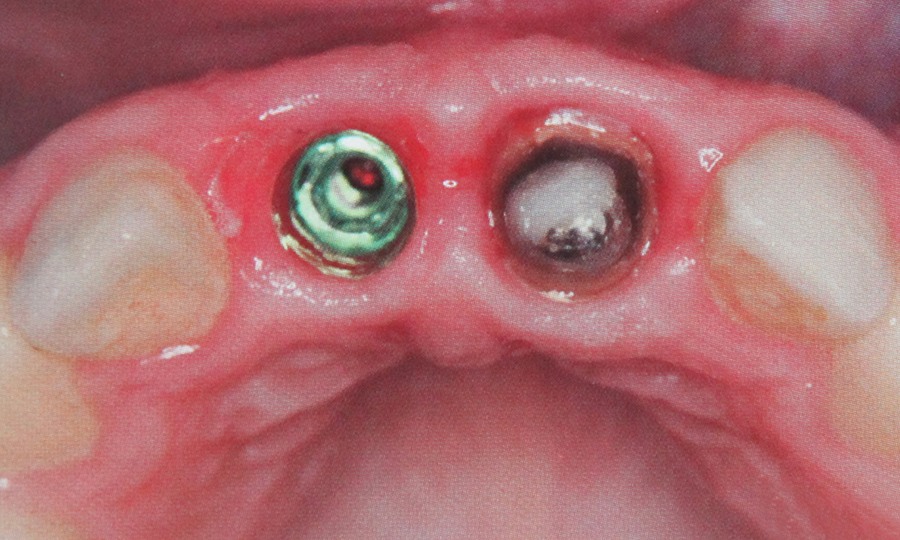

Implantele dentare reprezinta la ora actuala singura posibilitate de a inlocui dintii lipsa prin protezare fixa rezultand o dentitie foarte apropiata de dintii naturali. Implantele dentare sunt niste radacini artificiale realizate din titan care se insera in os. Dupa o perioada de aproximativ 6 luni perioada necesara pentru integrarea implantului, acestuia i se ataseaza un bont protetic pe care ulterior se fixeaza coronita de ceramica sau proteza.

Protetica pe implante este ramura implantologiei care se ocupa de faza restaurativa si componentelor planului general de tratament dupa inserarea implantelor.